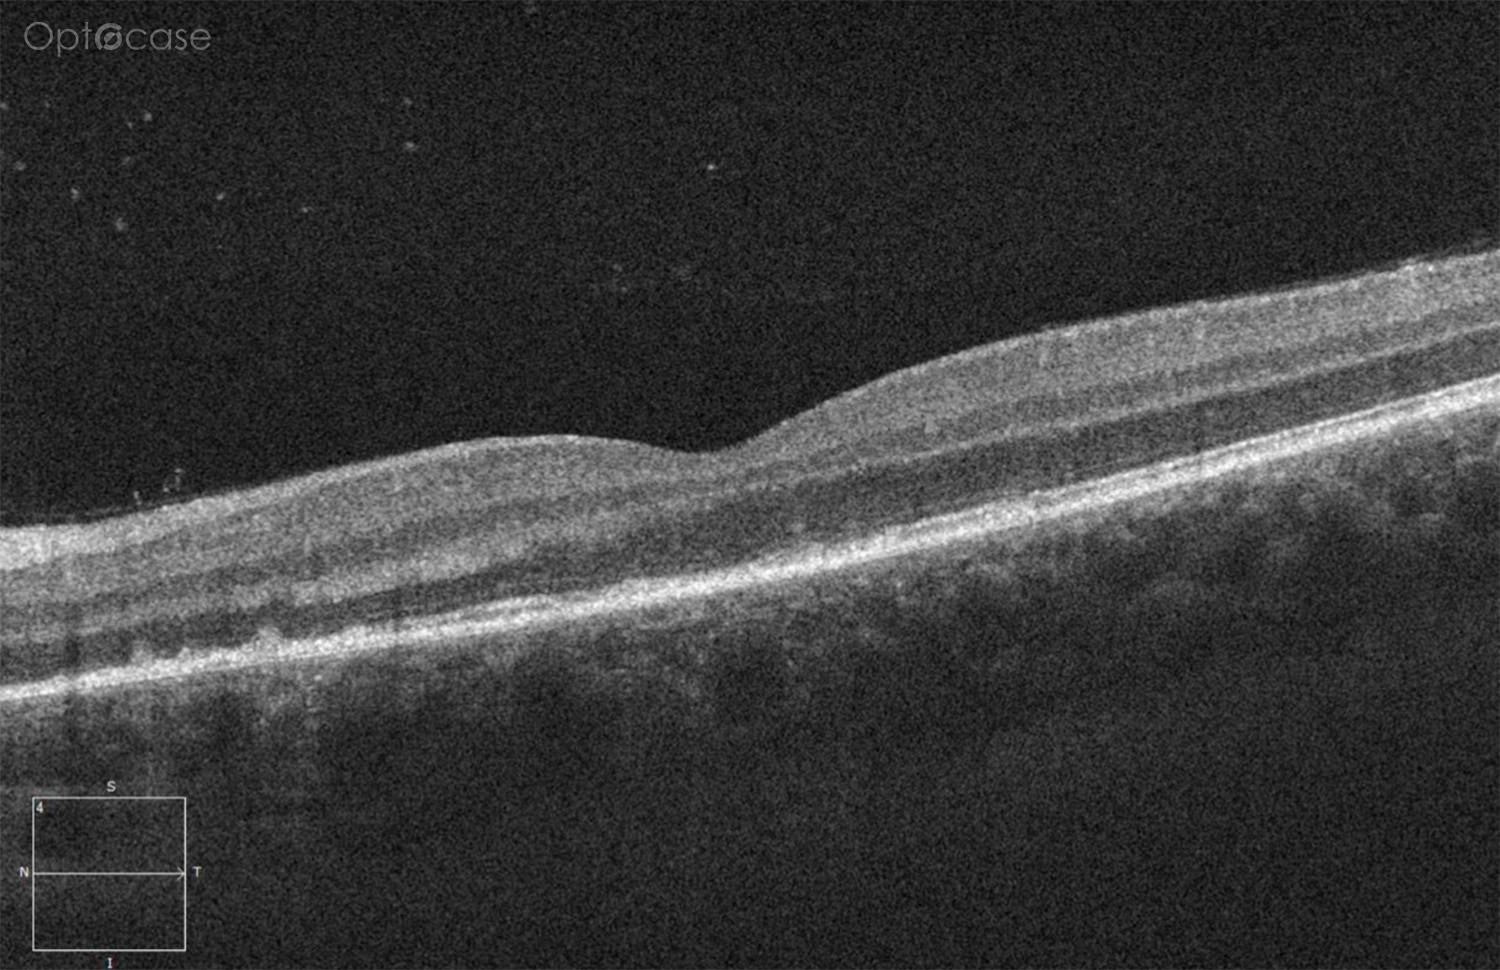

Here there is loss of the regular macular depression. There is a bright line present on the surface of the retina. In addition, there is separation of the retinal layers in the inner retina.

The patient was diagnosed with a schisis secondary to an epiretinal membrane. This complication is seen in over 50% of ERMs (video).